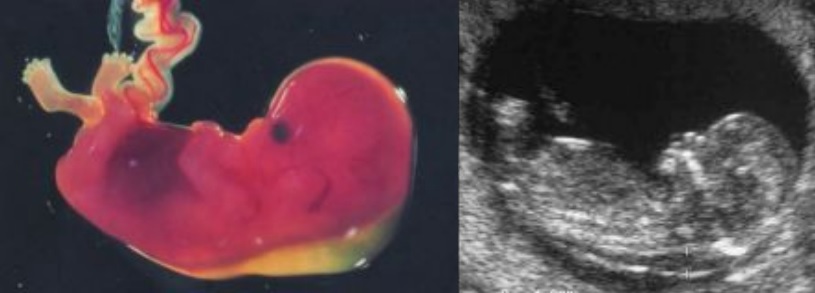

Αυχενική διαφάνεια

Η αυχενική διαφάνεια (ΑΔ) είναι η συλλογή υγρού στον τράχηλο του εμβρύου και, συγκεκριμένα, ανάμεσα στο δέρμα και στους ιστούς που καλύπτουν τη σπονδυλική στήλη.

Όλα τα έμβρυα μεταξύ 10 και 13 εβδομάδων έχουν μια ποσότητα υγρού, αλλά όταν αυτό είναι αυξημένο, το έμβρυο εμφανίζει μεγαλύτερο κίνδυνο για χρωμοσωμικές ανωμαλίες (συνήθως σύνδρομο Down), συγγενείς ανωμαλίες και, ειδικά, καρδιοπάθειες και γενετικά σύνδρομα.

Η ευαισθησία της μεθόδου για την ανιχνευση του μογγολισμού είναι περίπου 80%. Προσθέτοντας τη μέτρηση χοριακής γοναδοτροπίνης και PAPP-A στο αίμα της μητέρας, η ευαισθησία της μεθόδου αυξάνεται στο 90%.

Εάν το ρίσκο για χρωμοσωμικές ανωμαλίες που προκύπτει από την μέτρηση της αυχενικής διαφάνειας, του PAPP/A και της β-χοριακής είναι πιο μεγάλο από τον αντίστοιχο κίνδυνο που προκύπτει από την ηλικία της μητέρας, χρειάζεται περαιτέρω χρωμοσωμικός έλεγχος του έμβρυο με λήψη τροφοβλαστικού ιστού (CVS) η αμνιοπαρακέντηση.